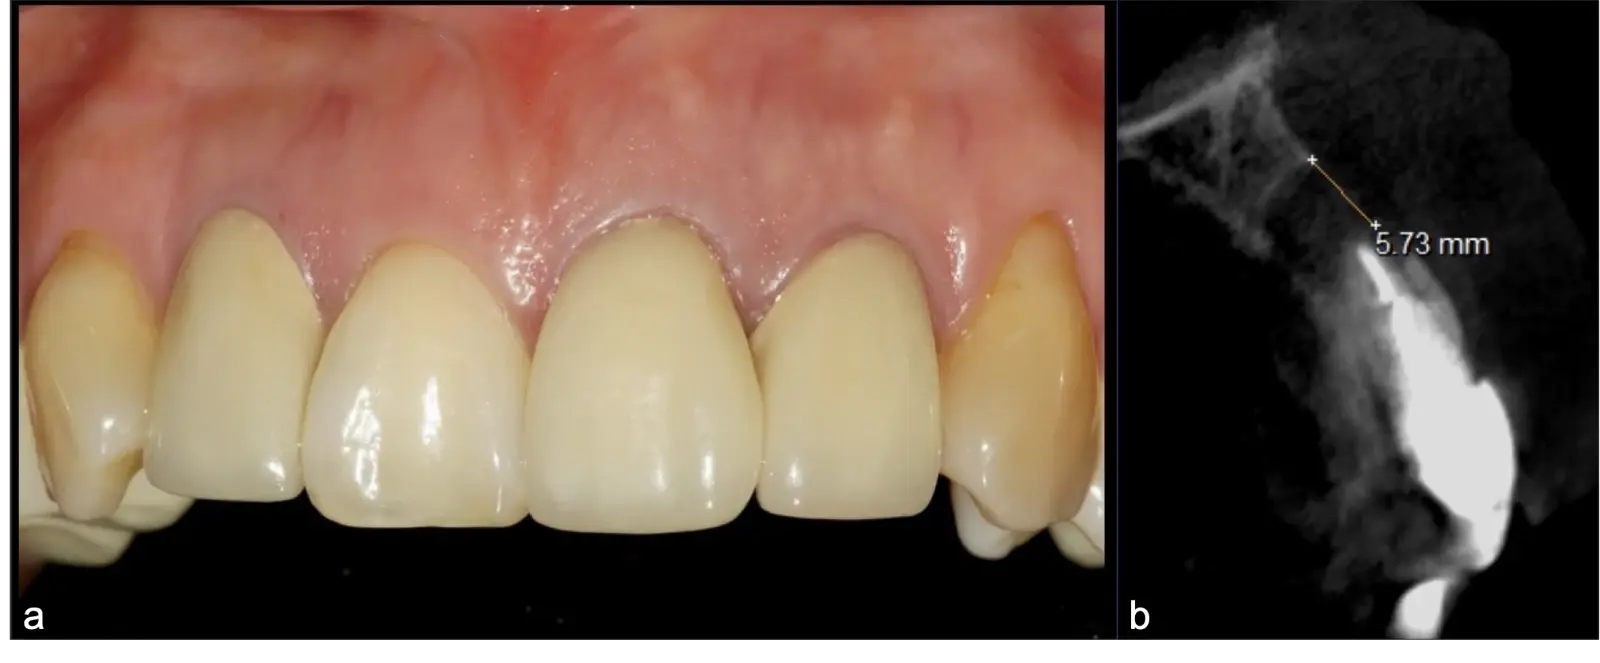

La microcirugía endodóntica apical busca conservar la mayor cantidad de longitud de raíz y de hueso circundante sano para no afectar la estabilidad de la pieza.11 Por ello, es ideal el uso de microscopios, elementos de magnificación, instrumental específico (insertos de ultrasonido endodónticos) y materiales de sellado eficientes para el tratamiento retrogrado. Su éxito es alto y evidencia una cicatrización ósea completa en el 74% de los casos al año de tratamiento.12 Cabe destacar que este logro está asociado también, a predictores propios de cada paciente, como la edad, tipo de pieza, profundidad de sondaje y extensión de la lesión.1 El uso complementario de la tomografía computarizada es resaltante como el instrumento imagenológico de elección para la etapa de planificación microquirúrgica,13 ya sea para una ejecución a mano alzada o con guías prefabricadas.14,15

Frente a ello, se debe decidir entre un retratamiento de conductos, que involucra un probable retiro del espigo y de la prótesis cementada, o un abordaje microquirúrgico apical. El primero estima un éxito promedio del 80% y mayor riesgo de fracturas radiculares con posterior pérdida del diente; mientras que el segundo, tiene un éxito del 92%9 y brinda como principal ventaja una visualización y manipulación directa de la lesión problema.10